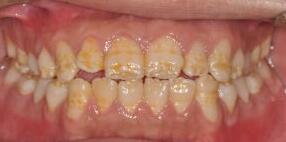

【釉质发育不良的牙齿能否洗白?】

比如氟斑牙、四环素牙等疾患,会引起釉质发育不良。牙面往往不是光滑、洁白的外观,不仅有些“横道”样的粗细不一的缺损,还有条状、斑片状以及整个牙冠内部的着色。

这样的外形和着色都是先天发育形成,决然不是后期沉积在表面的“脏东西”。

我们洗牙后,只能去除牙石这些“脏东西”,露出你原本就存在的“不好看”的牙齿表面!

不可能把你的牙“变”白!!